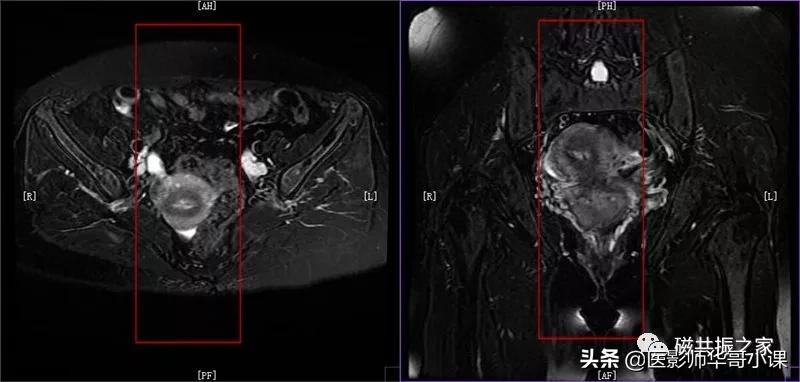

子宫MRI扫描前应先行1-2个大范围的 全盆腔 扫描序列,通常为大范围的T1WI和T2WI 压脂序列;在冠状位和矢状位上定位,按照常规的横轴位扫描即可。

行大范围扫描的目的:

1.了解盆腔内病变的大体情况。

2.视察盆腔内出血、转移、周围侵犯等情况。